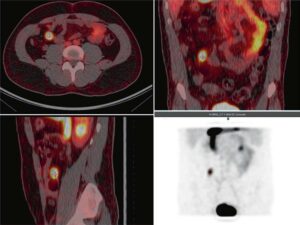

Scintigrafia con leucociti marcati 99mTc-HMPAO in una paziente di 64 anni con gonartrosi severa al ginocchio destro, dolore, tumefazione e limitazione funzionale. Quattro anni prima era stata trattata con antibiotici ad alte dosi per positività del liquido sinoviale a Staphylococcus epidermidis. In seguito all’aumento degli indici infiammatori (VES e PCR), è stata richiesta la scintigrafia con 99mTc-HMPAO-WBC per escludere un’infezione prima dell’impianto protesico.

Scintigrafia con leucociti marcati

Le immagini SPECT/CT fuse in proiezioni assiale (sinistra), sagittale (centro) e coronale (destra), acquisite a 3 ore (riga superiore) e 20 ore (riga inferiore) dopo l’infusione di leucociti marcati con 99mTc-HMPAO, mostrano un accumulo moderato e diffuso nel femore distale e nella tibia prossimale destra. Il pattern temporale evidenzia una diminuzione progressiva della captazione.

Le immagini planari acquisite a 30 minuti, 3 ore e 20 ore dopo l’infusione del radiofarmaco mostrano un’intensa captazione al ginocchio destro, con incremento progressivo nel tempo. L’acquisizione SPECT/CT ha permesso di distinguere due focolai:

- uno con trend crescente nel tempo, localizzato in un’area di versamento peri- e intra-articolare, compatibile con artrosinovite settica;

- uno con captazione più evidente a 3 ore e decrescente a 20 ore, localizzato nel femore distale e nella tibia prossimale destra, suggestivo di infiammazione asettica associata a gonartrosi.

La scintigrafia con 99mTc-HMPAO-WBC offre un’elevata specificità per distinguere:

- infezione: captazione che aumenta e si estende nel tempo;

- infiammazione asettica: captazione iniziale che può aumentare fino a 3–4 ore, ma tende poi a diminuire.

Le immagini SPECT/CT sono particolarmente utili per localizzare il processo infiammatorio/infiammatorio e identificarne la distribuzione tra tessuti molli e strutture ossee.